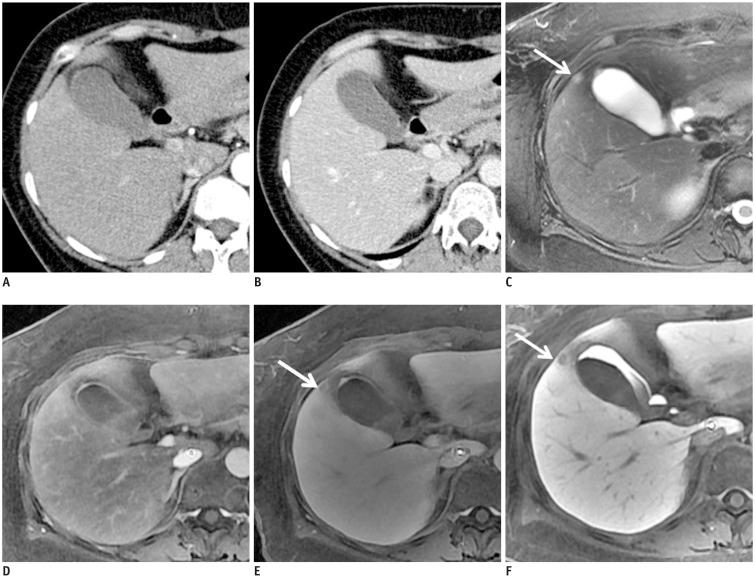

To compare the diagnostic performance of gadoxetic acid-enhanced magnetic resonance (MR) imaging with that of triple-phase multidetector-row computed tomography (MDCT) in the detection of liver metastasis.

For both readers, average JAFROC figure-of-merit (FOM) was significantly higher on the MR image sets than on the MDCT images: average FOM was 0.582 on the MDCT, 0.788 on the dynamic-MRI set and 0.847 on the combined HBP set, respectively (p < 0.0001). The differences were more prominent for small (≤ 1 cm) lesions: average FOM values were 0.433 on MDCT, 0.711 on the dynamic-MRI set and 0.828 on the combined HBP set, respectively (p < 0.0001). Sensitivity increased significantly with the addition of HBP in gadoxetic acid-enhanced MR imaging (p < 0.0001).

Gadoxetic acid-enhanced MRI shows a better performance than triple-phase MDCT for the detection of hepatic metastasis, especially for small (≤ 1 cm) lesions.